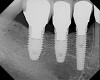

When three or more implants in a row are planned, concepts of spacing and angulations, parallelism in all dimensions, proximity to anatomic structures, and relationships between implant positions and planned restorations are all significant considerations. CT/CBCT-guided surgery allows for the ideal placement of multiple dental implants according to the planned restoration while taking these issues into consideration (Figure 2 and Figure 3). Implants can be placed flaplessly and immediately loaded.6-8,11-14,25-29